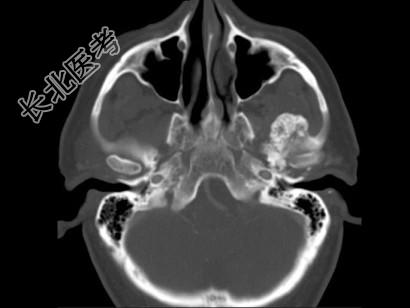

- 多项选择题男,60岁, 张口受限半年,CT检查如图所示, 正确的描述或诊断是 ( )

A、左侧颞颌关节周围软组织内见较多致密钙化影

B、左侧颞颌关节软组织未见肿胀

C、左侧颞颌关节面(颞骨面)骨质增生明显

D、左侧颞颌关节滑膜骨软骨瘤病

E、颞颌关节功能紊乱